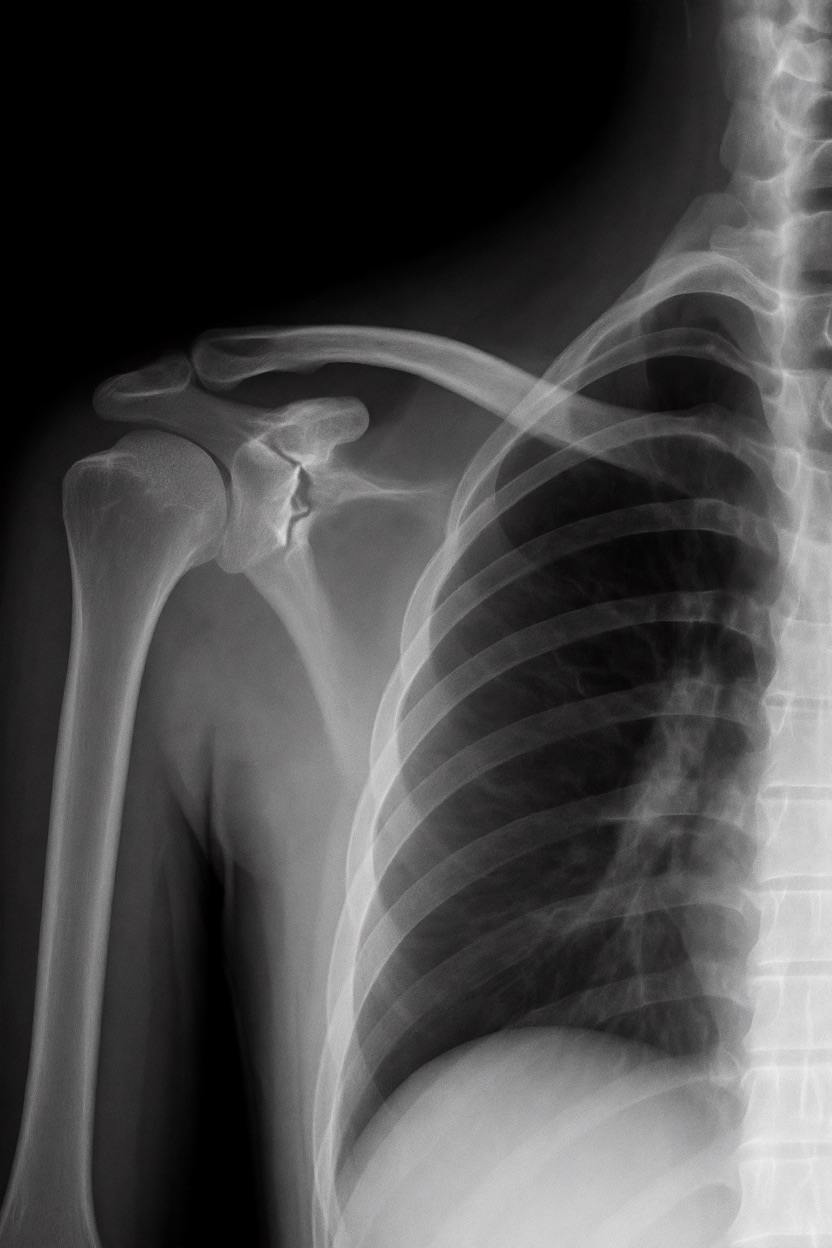

アートや写真の編集用に設計されたFlux Kontextのようなモデルを、医療画像、たとえば「単純な」骨折の赤色マーキングに使用できるか?

有効な用途

- 医療画像におけるAIプロトタイプやテスト

- X線の「疑わしい」領域を視覚的に目立たせる(実験的・創造的アート、エキゾチックなツール xD)

- 感度 vs 偽陽性のバランスを実験するための教育的・実験的素材